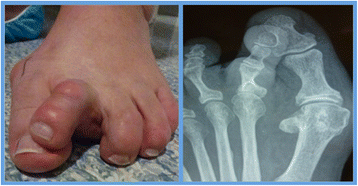

Simple digital deformity included pathology, which was confined to the phalanges and soft tissue structures involving the interphalangeal joints (Figure 1). Surgical procedures in this group included percutaneous phalangeal osteotomies and/or osteectomy with or without percutaneous lengthening/release procedures to flexor/extensor tendons and capsular releases as required.

Figure 1

Simple digital deformity (pre-operative). Flexion deformity is seen at the distal interphalangeal joint of the right 3rd toe clinically and radiographically.